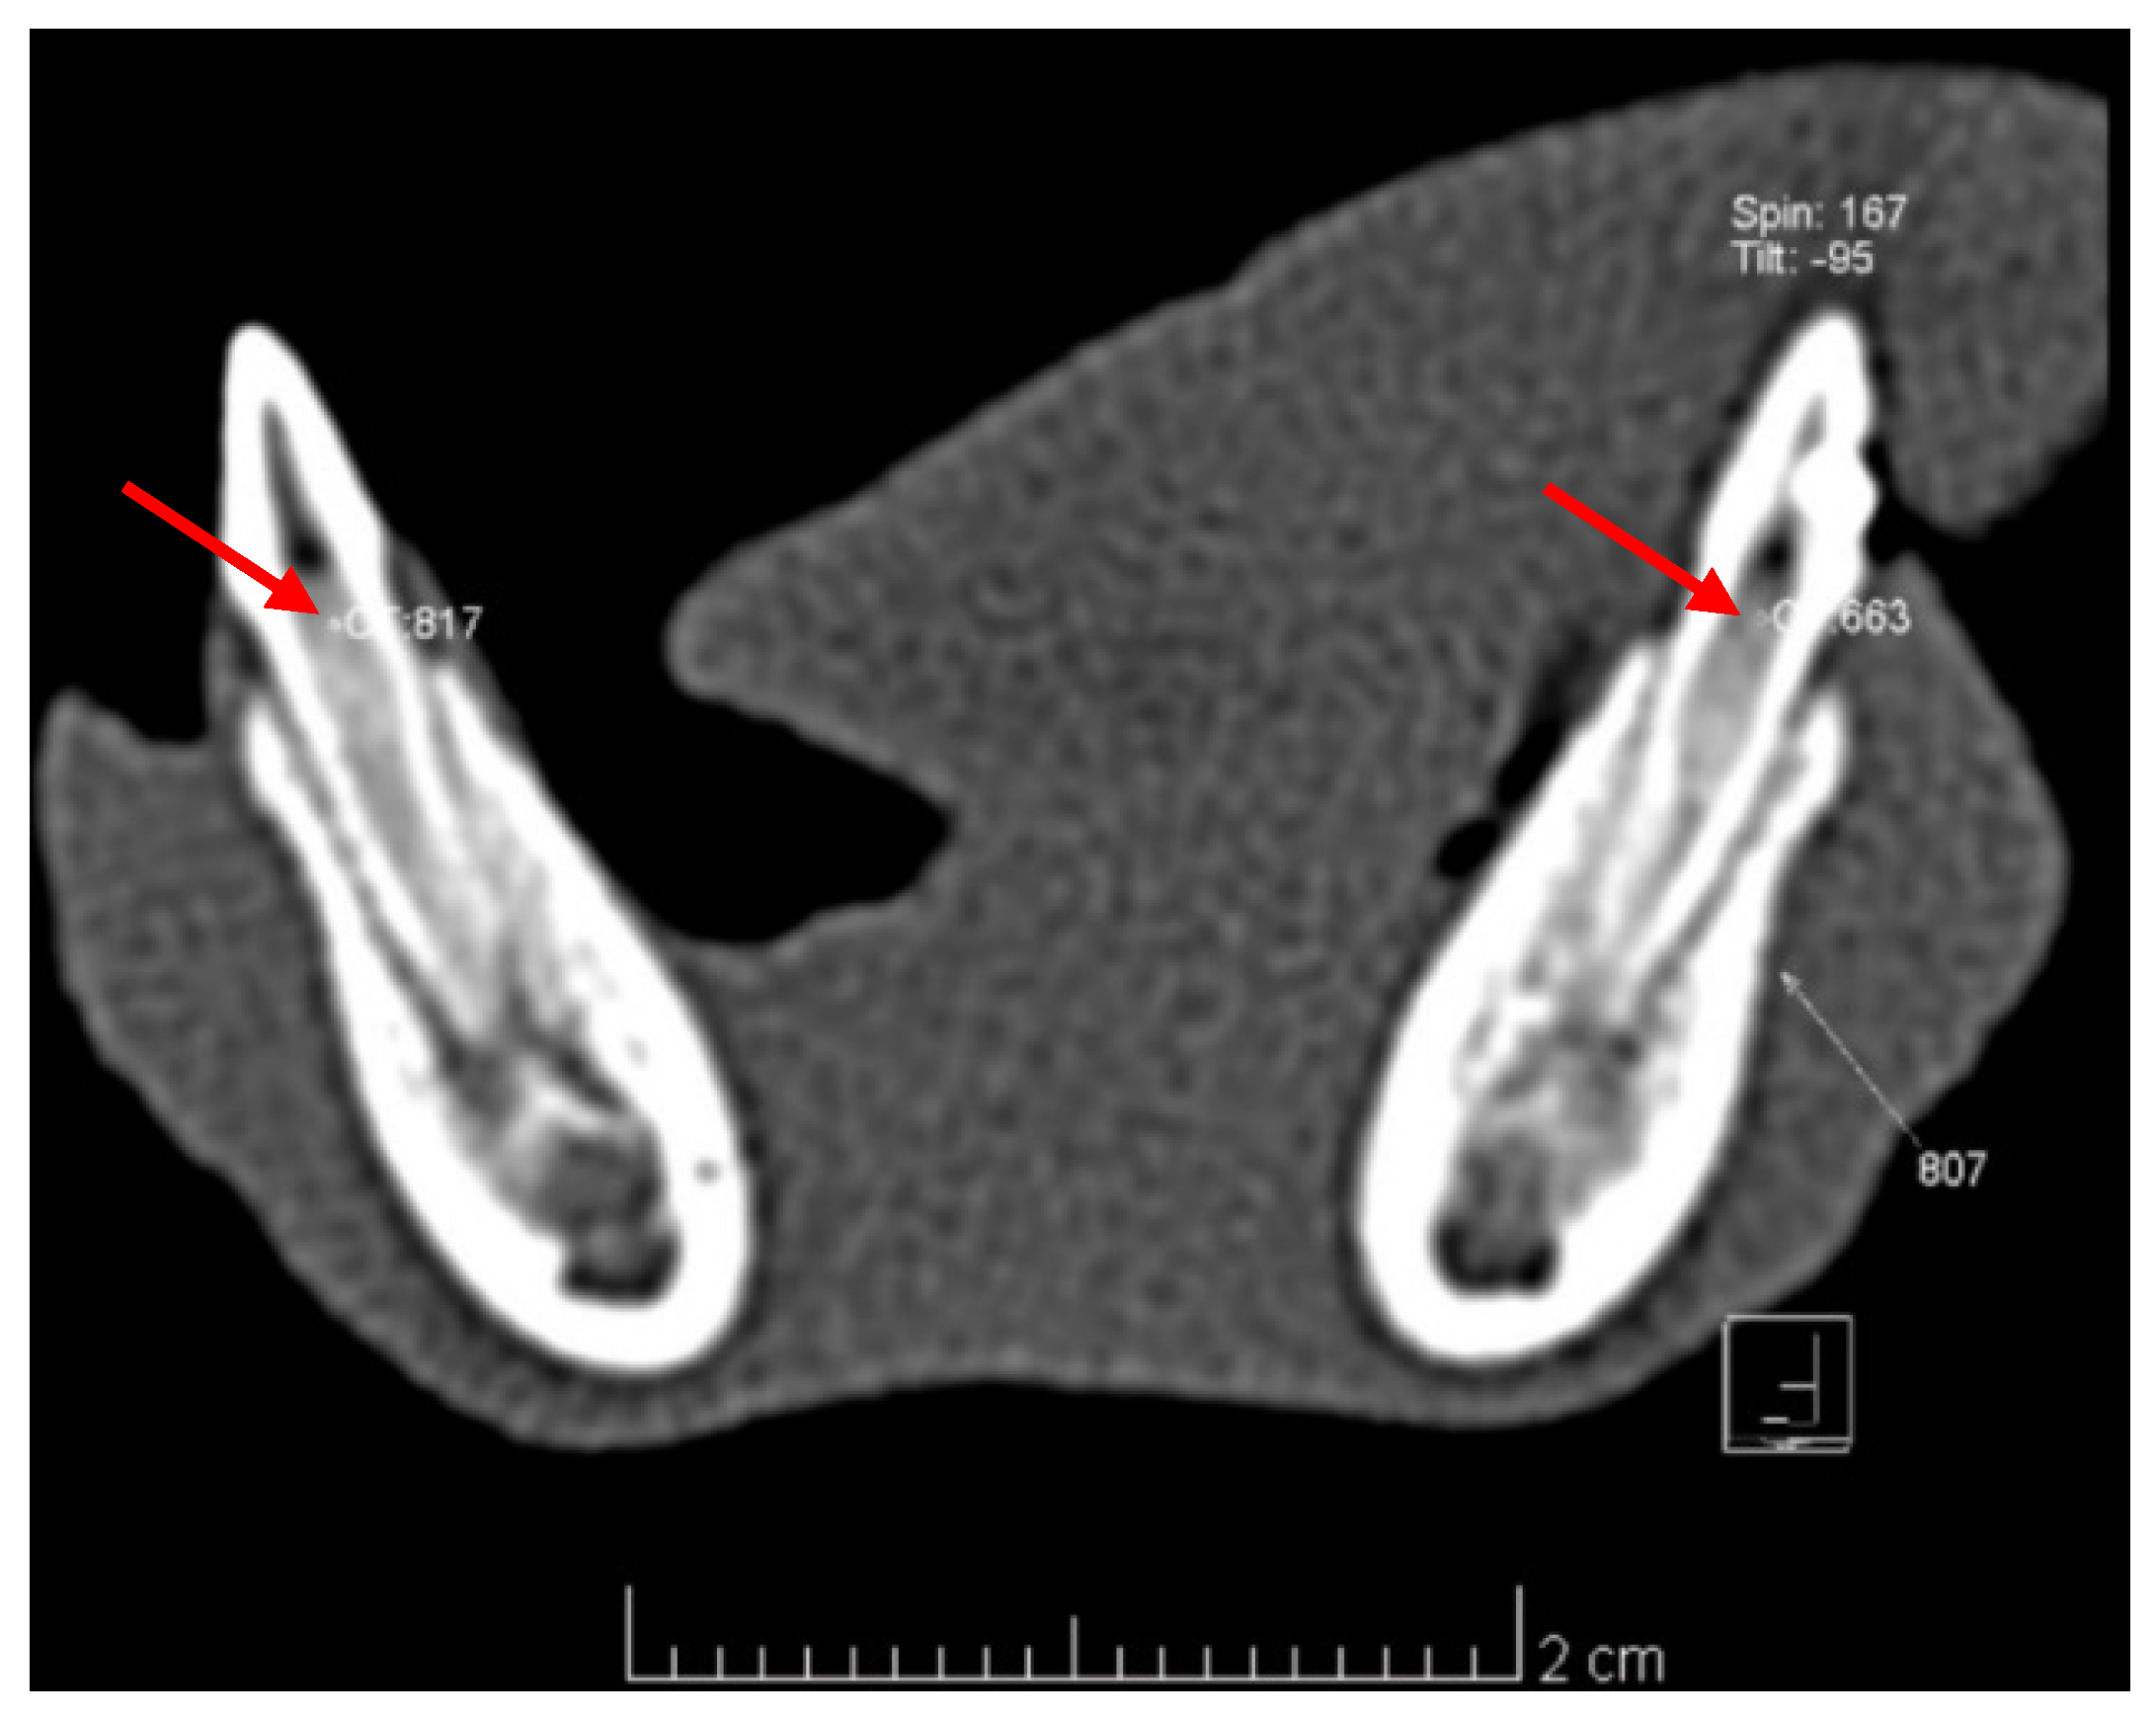

3.2.1. Imagistic Research

| Treated/Control Group | Average Values of Pulp Density |

|---|---|

| 804/704 | 328.87 HU/506.25 HU |

| 806/706 | 579.12 HU/698.37 HU |

| 807/707 | 694.37 HU/622.62 HU |